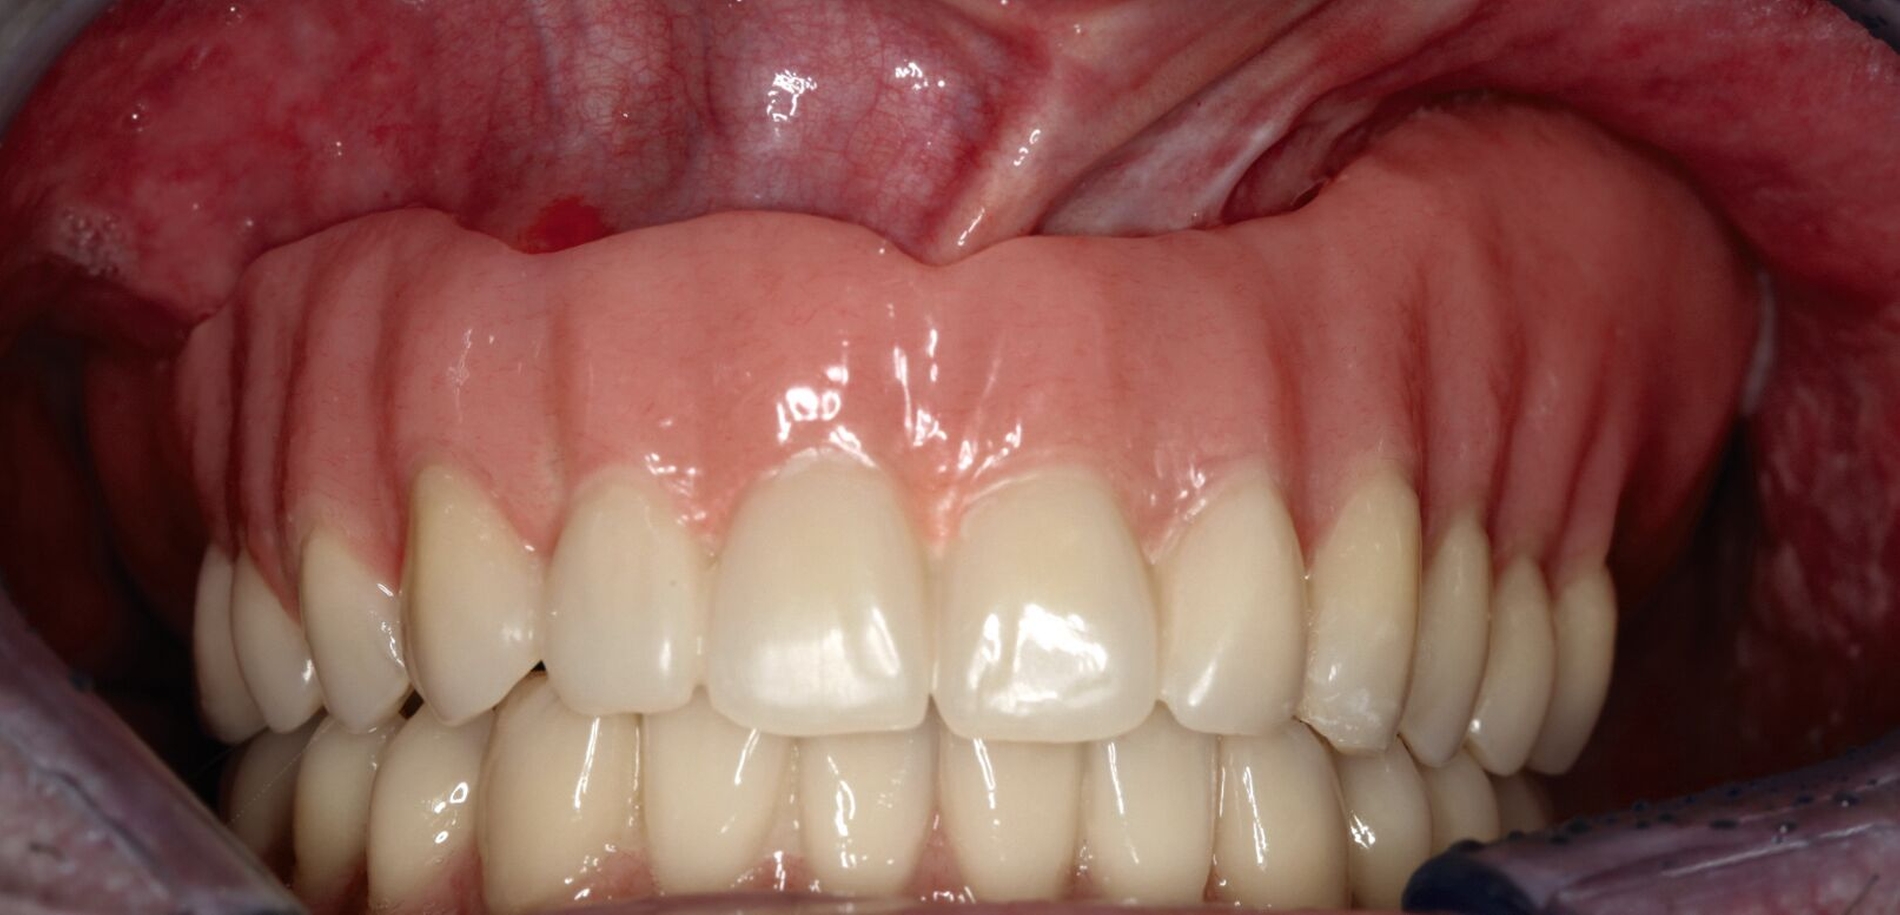

Wenn möglich und vom Patienten gewünscht, wird eine chirurgische Rekonstruktion gewählt. Hier wird beispielsweise mit mikrovaskulär anastomosierten Fibula- oder Beckenkammtransplantaten nach erfolgter Oberkiefer(teil-)resektion der vollständige Verschluss der oro-nasalen Verbindung angestrebt [Dos Santos et al., 2018]. Durch den Verschluss wird die Sprechfunktion wiederhergestellt. Die knöcherne Rekonstruktion ermöglicht die Insertion von Implantaten in den knöchernen Anteil des Transplantats [Wijbenga et al., 2016], wodurch die Möglichkeit für einen implantatgetragenen Zahnersatz geschaffen wird.

Bei der Tumornachsorge zeigt sich ein großer Vorteil des prothetischen Defektverschlusses: Zusätzlich zur Bildgebung kann mithilfe klinischer Inspektion frühzeitig ein Rezidiv entdeckt werden [Ali et al., 1995; Moreno et al., 2010]. Beim prothetischen Defektverschluss kann eine Acrylat-Obturator-Prothese gewählt werden, die je nach Mundöffnung ein- oder mehrteilig gestaltet ist und die auch verlorengegangene Zähne ersetzt. Alternativ gibt es die zwingend zweiteilige Möglichkeit eines Defektverschlusses über einen Silikon-Obturator mit einer darauf sitzenden Prothese zum Ersatz von Zähnen.

Bei einer Obturator-Prothese (Abbildung 2) erfolgt der Defektverschluss mittels hartem Acrylat-Prothesenkunststoff. Sie kann im Zenit offen oder geschlossen gestaltet sein. Der Halt wird über Klammern, Teleskope oder eine implantatgetragene Verankerung erzielt. Bei vollständiger Zahnlosigkeit ist eine Obturator-Prothese nicht zu empfehlen, da der gewöhnlich genutzte Saugeffekt nicht hergestellt werden kann. Bei zahnlosen Patienten, die keine Implantate erhalten können oder sollen, ist es sogar empfehlenswert, den Defekt nicht zu rekonstruieren, damit Unterschnitte für einen Silikon-Obturator genutzt werden können.